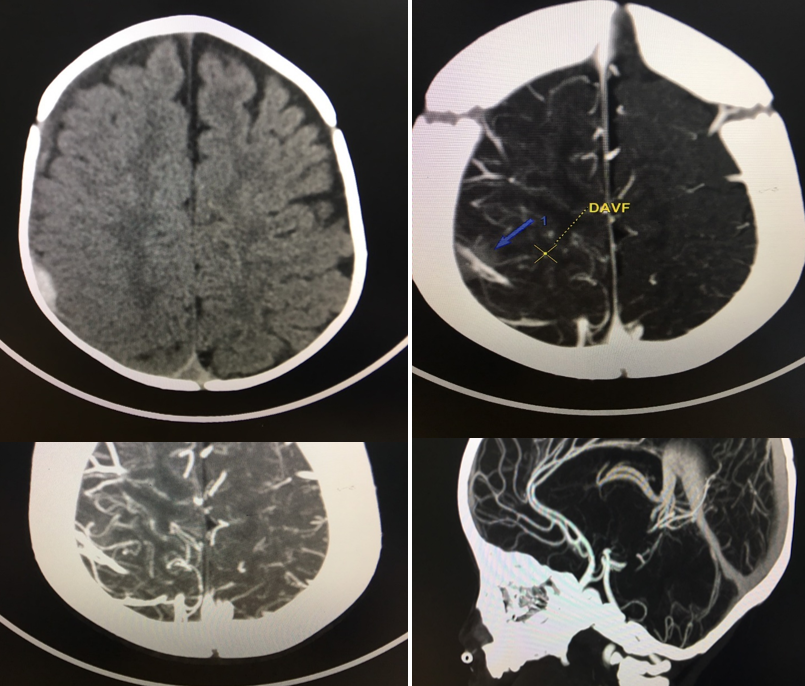

Ngày 12/3/2021, Bn N.M.Q sinh ngày 12/08/2020 ở An Dương - Hải Phòng nhập viện trong tình trạng quấy khóc, thóp phồng, nôn nhiều, không sốt, không co giật và được chỉ định chụp CLVT sọ não 64 dãy tại khoa Chẩn đoán hình ảnh Bệnh viện Trẻ Em Hải Phòng. Hình ảnh tụ máu dưới màng cứng bán cầu não bên phải nghi ngờ có dị dạng mạch não do bệnh nhân không có tiền sử chấn thương và không mắc các bệnh về máu. Sau đó được chỉ định chụp CLVT 64 dãy có dựng mạch não có tiêm thuốc cản quang Xenetix 300mgI/ml và cho kết quả: “Tụ máu dưới màng cứng bán cầu não bên phải nghi do rò động mạch - màng cứng (DAVF)”.

Hình ảnh chụp CLVT 64 dãy mạch não của Bn N M Q tại khoa Chẩn Đoán Hình ảnh: